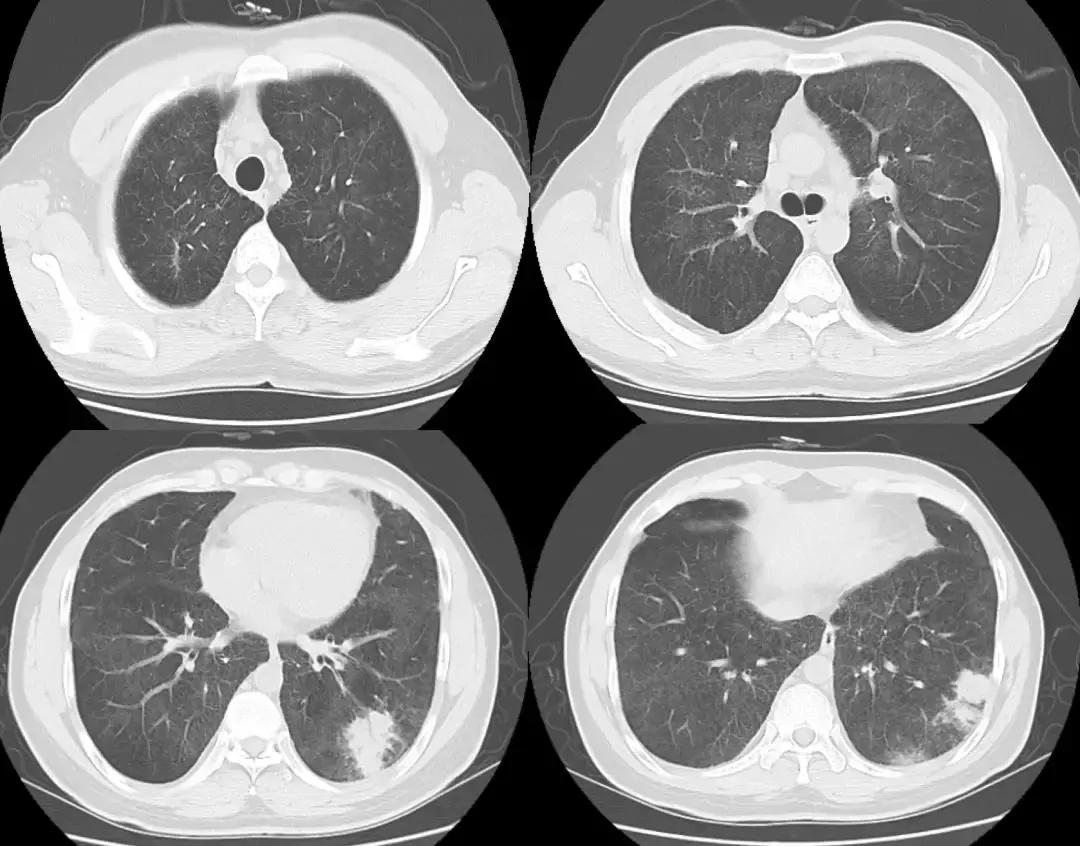

2018-01-22行支气管镜检查:示两侧支气管粘膜充血明显,可见少量白色分泌物,充分吸引;于左下叶生理盐水20ml灌洗2次,回吸收均约10余ml;左上叶、左下叶刷检,刷片共6张。(气管镜报告如下图)。

隆突 右上叶

右中叶 右下叶

左上叶 左下叶

支气管镜病理检查如下